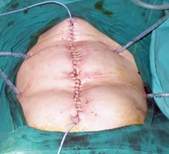

Closed systems for hyperthermic intraperitoneal chemotherapy (Courtesy Dr. V. Penopoulos)